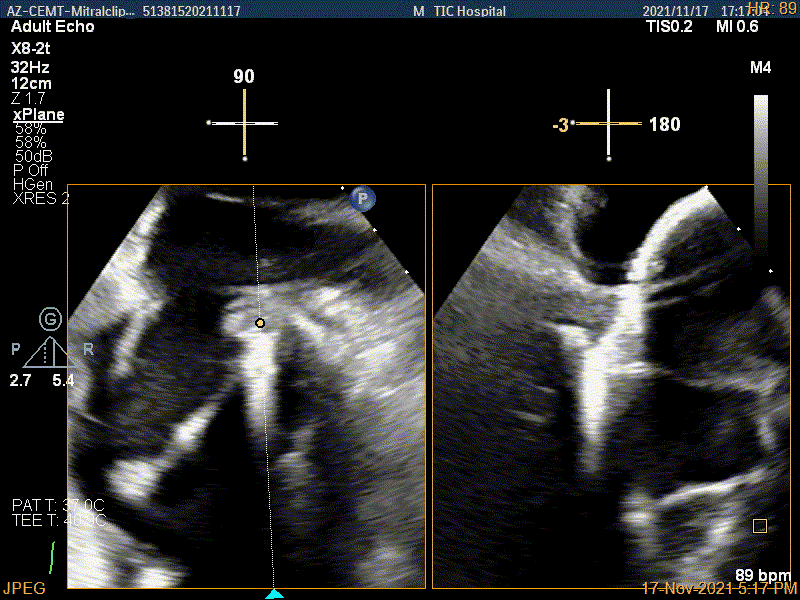

确定房间隔穿刺点

2D视图观察夹子经过大鞘进入左房内

3D视图下进夹子并建立trajectory

3D视图打开夹子

Multivue视图下将夹子正对AC区并调节Rotate

X-plane:下夹子尝试捕获靠近AC区脱垂瓣叶